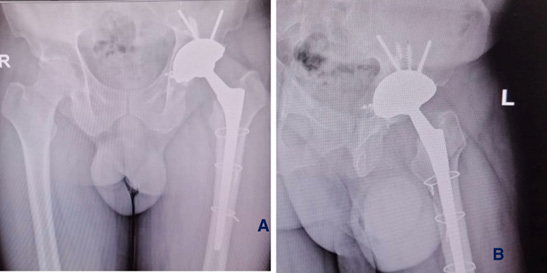

Figure 3: Post-operative plain radiograph (anteroposterior view) of the right hip showing an acetabular cup with a screw and a well-fixed uncemented femoral stem. (A) fluoroscopic image intra-operative (B) immediate post-operative X-ray.

Postoperative recovery was uneventful. The patient was mobilized with toe-touch weight-bearing using a walker on the first postoperative day. At one-year follow-up (Figure 4), the patient showed marked improvements in pain relief, hip range of motion, and functional status, with a significant increase in the Harris Hip Score (Figure 4).